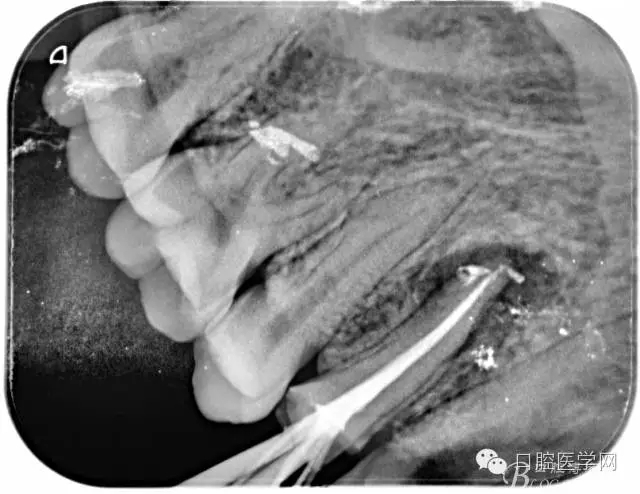

根管的解剖界限是从髓室根管入口到根尖部牙本质- 牙骨质交界处(生理性根尖孔) 。理想的根管充填应该是对生理性根尖孔冠方以上进行严密的三维封闭。临床上根据X线牙片判断根管充填的质量。牙片上充填材料与根管壁紧密接触一般被认为充填严密。关于充填止点,由于牙本质- 牙骨质界离根尖孔外表面平均距离为0. 5~0. 7 mm,同时相当多的根尖开口并不位于X线片的根尖处。因此临床上认为材料充填至距X线片牙根最尖端0. 5~1 mm (也有认为0. 5~2mm)为适填。

为达到更为理想的根充效果,研究人员和牙髓病医生一直在探索根管充填技术,并且发展出多种可供选择的方法。Ingle]将其归纳为3 类: ①“牙胶尖+封闭剂”式; ②“根尖1 /3充填”式; ③“注射或螺旋充填”式。目前临床广泛采用的主要是“牙胶尖+封闭剂”方式。按照充填压力的方向(侧向或垂直)不同和牙胶温度(冷或热)不同,根管充填有2 种基本技术:冷牙胶侧方加压充填和热牙胶垂直加压充填。现有的各种充填方法均是这2 种基本方法基础上的发展或改良。医生可根据方法的优缺点以及个人习惯选择使用。